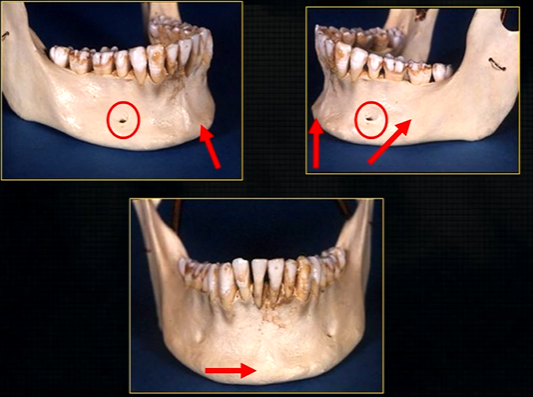

mandible - the lower jaw

mental prominence

body

mental foramina

dense bony prominence of the external oblique ridge

angle

coronoid process - and ascending rami on both sides????

mental foramen - black radiolucency - near 1st and 2nd premolars